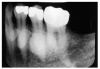

Figure 2 illustrates advanced enamel caries on the mesial surface of the premolar.

Figure 2 - Advanced Enamel Caries

Figure 2